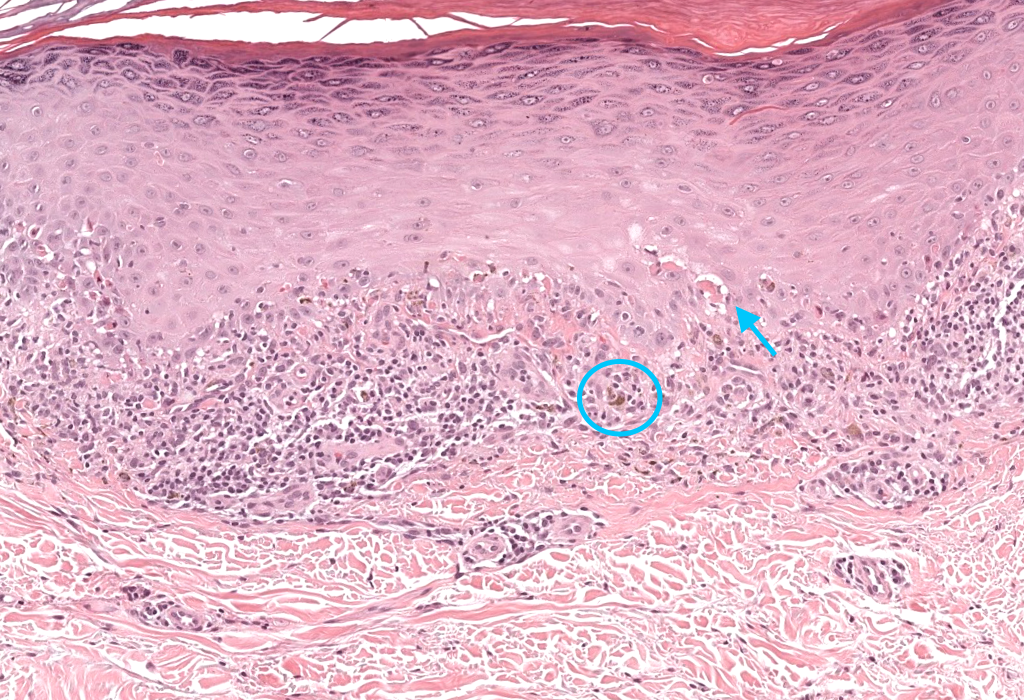

- Biopsia

- Tipo: punch 4–5 mm piel / incisional mucosa.

- Localización: lesión activa reciente / borde de erosión en LPO.

- Segunda biopsia en medio para IFD si duda con lupus, penfigoide, pénfigo.